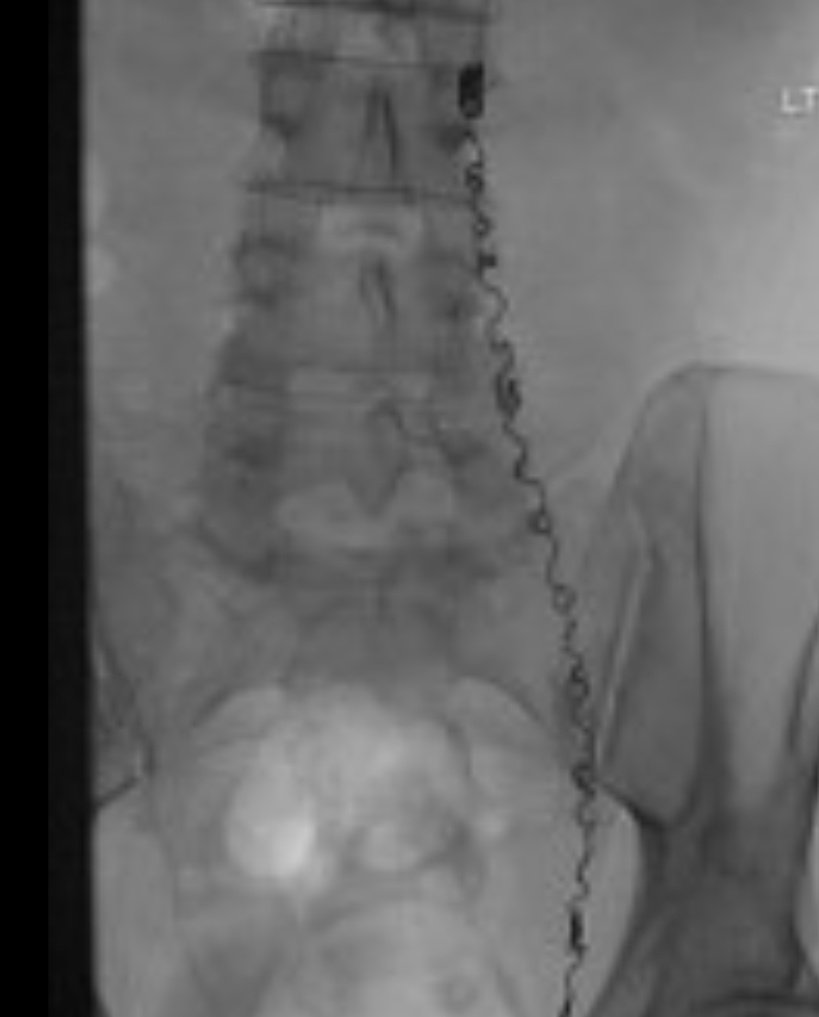

2️⃣الاشعه التداخليه:

طريقه جيده جدا لعلاج الدوالي بدون تخدير بنسبة نجاح تصل الى ٩٨% عن طريق سد الاورده بوضع قسطره داخليه وتجليط الوريد من الداخل.

مناسبة جدا لمن قام بعمل عمليه سابقا بوجود التصاقات وغيرها ..